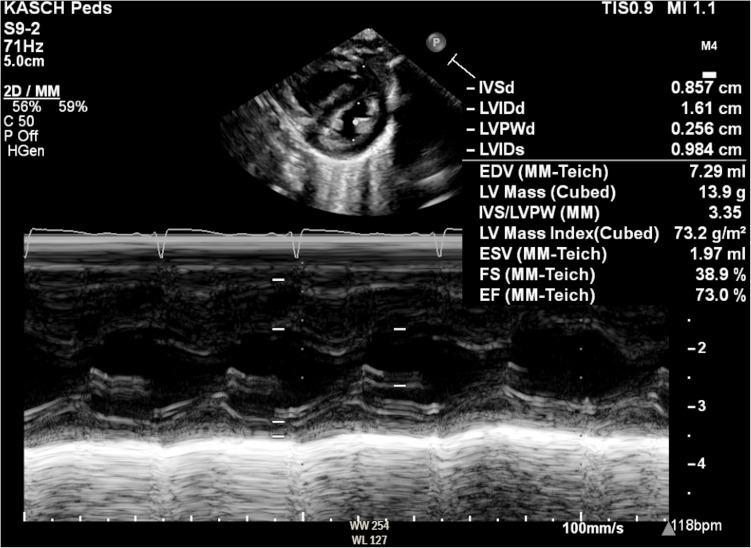

Abstract Image